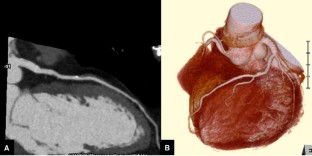

A 75-year-old female was admitted to our hospital with sudden back pain and right leg ischemia. Computed tomography showed acute type A aortic dissection with the occlusion of the right common iliac artery. The patient was treated with ascending aorta replacement and femoro-femoral bypass. Three hours after the operation, the patient went into a sudden shock. Electrocardiogram showed ventricular tachycardia and ventricular fibrillation. Percutaneous cardio-pulmonary support was administered and coronary arteriogram (CAG) was proceeded for evaluation of the coronary arteries. Although CAG revealed normal coronary arteries, intravascular ultrasound showed mobile intimal flap at left main coronary artery trunk, suggesting dissection of the coronary artery. Percutaneous coronary intervention of the left main coronary artery trunk was performed. The patient recovered from shock and was discharged from the hospital without any major complication.

Fig. 3